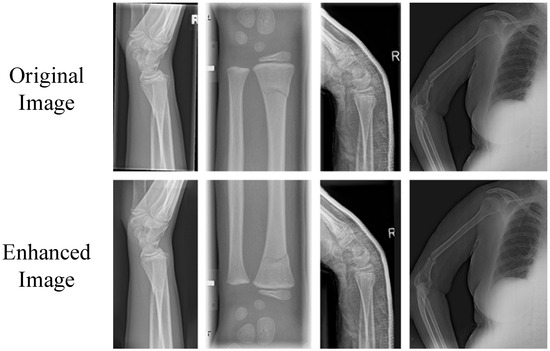

- First of all, multiple public datasets were collected. Subsequently, a data augmentation technique combining random rotation, translation, flipping, and content recognition filling was proposed. This was performed to effectively alleviate the problem of data scarcity and thereby enhance the generalization ability of the model.